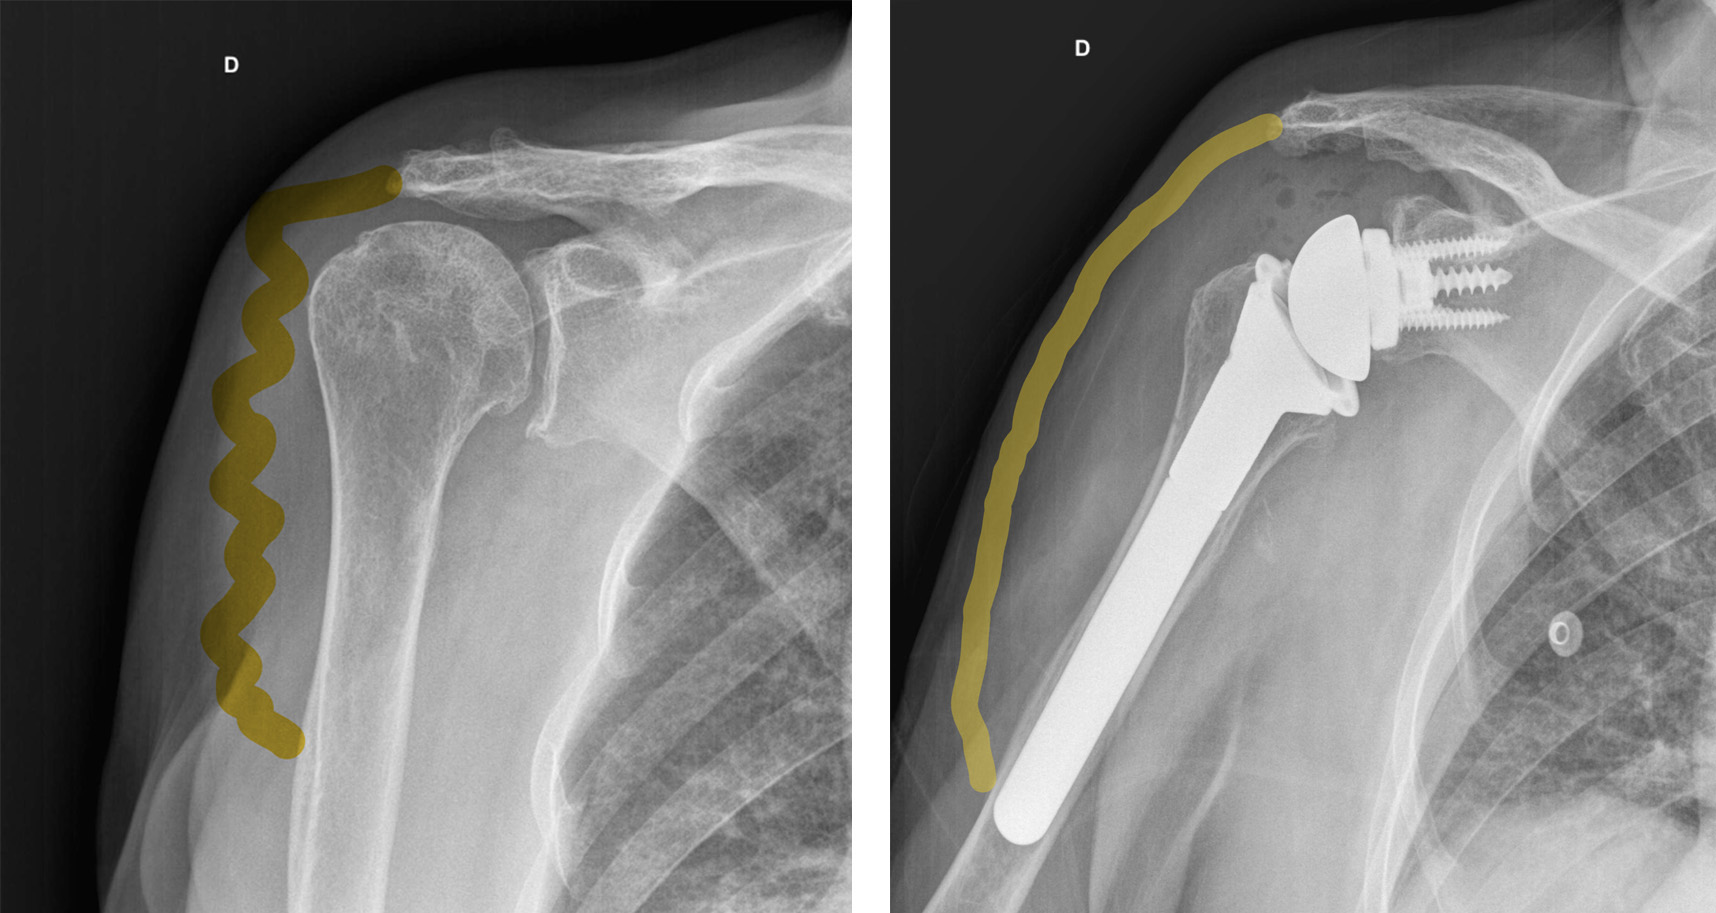

Em pacientes com alteração da coifa dos rotadores como rotura ou fratura, o músculo deltoide puxa a cabeça do úmero para cima e fora da articulação, de modo que a elevação do braço se torna difícil ou impossível. Isto pode levar a artrose que é denominada artropatia por rotura da coifa dos rotadores (fig. 4).

Artropatia por rotura da coifa dos rotadores – artrose gleno umeral com escape superior da cabeça no contexto de rotura maciça da coifa dos rotadores.

Normalmente o diagnóstico é feito através da radiografia (fig. 6) e tomografia computadorizada (para melhor determinar a versão da glenoide ou seu stock ósseo) (fig. 7) ou ressonância magnética (melhor avaliar integridade da coifa dos rotadores e infiltração gorda).